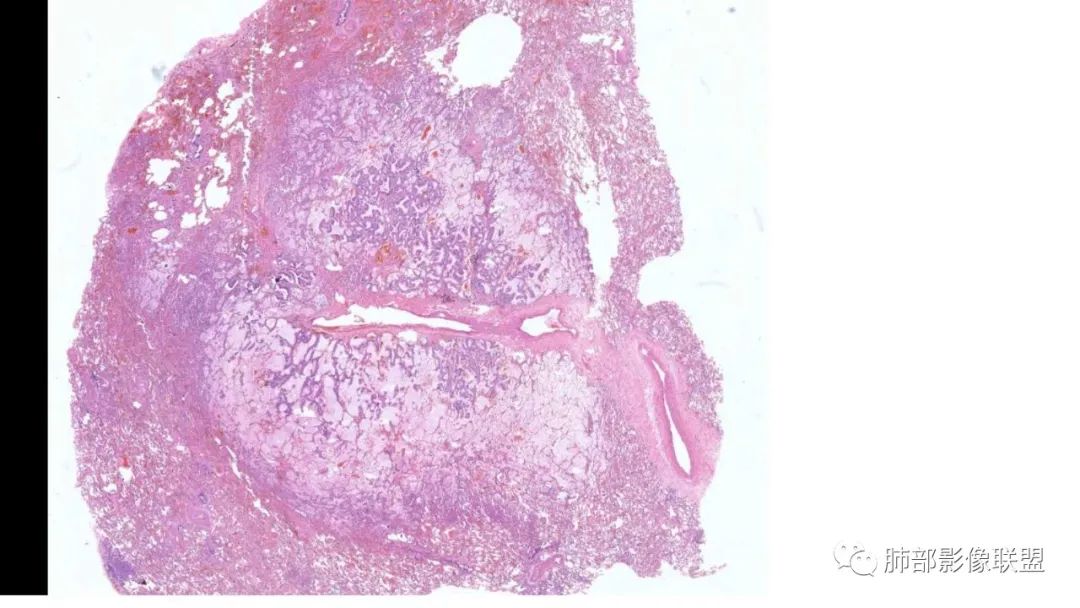

粘液腺癌影像上分为:结节型及斑片型/混合(肺炎型)。

一、结节型粘液腺癌和普通腺癌类似,重视体检及复查不易遗漏

1.多位于胸膜下,90%位于胸膜下,70%下叶胸膜下(125例)

2.病变周围GGO,边界清楚或稍模糊。圆圈征、草帽征、树上蘑菇征等。

3.结节型发展缓慢,淋巴结转移少见。

4.无明显强化或低强化。